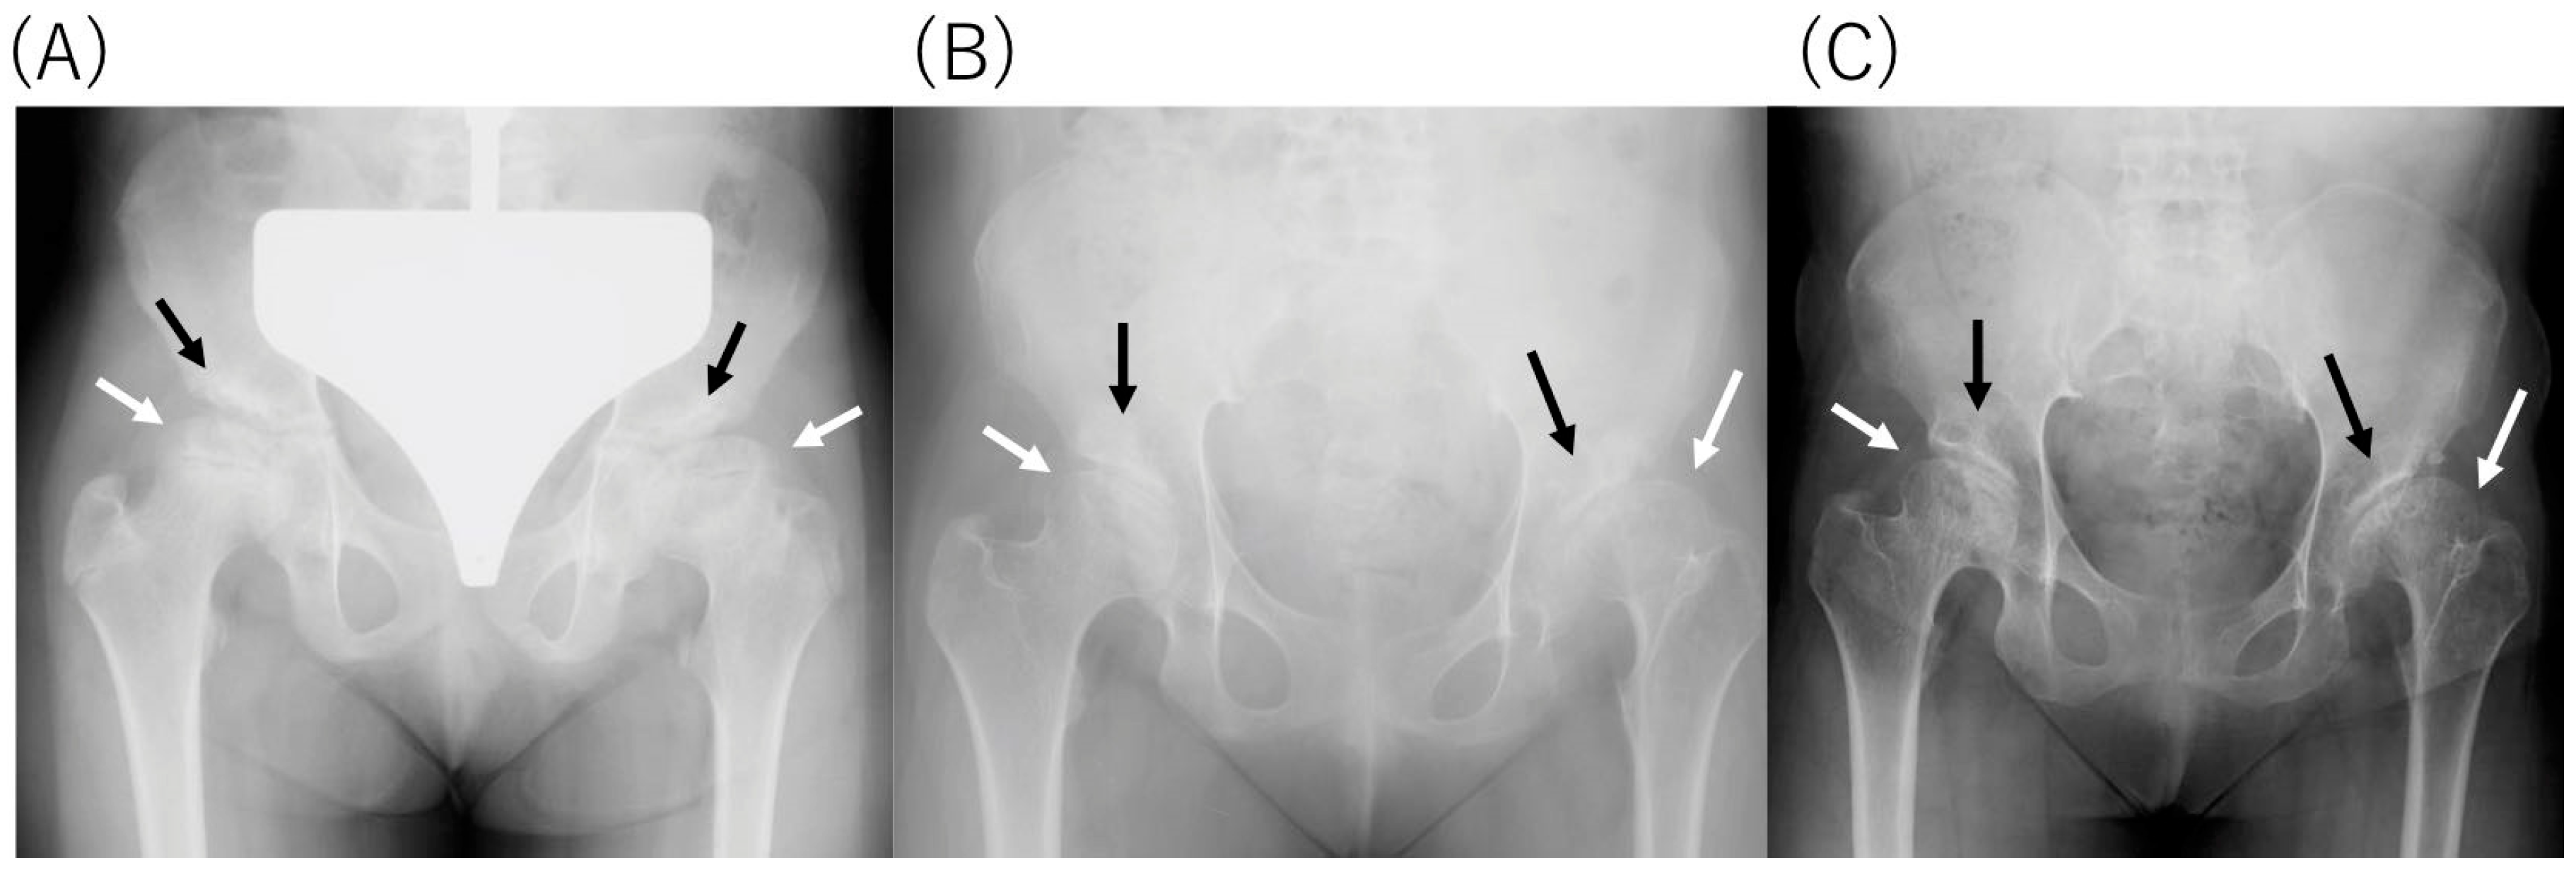

2.4. Radiological Findings